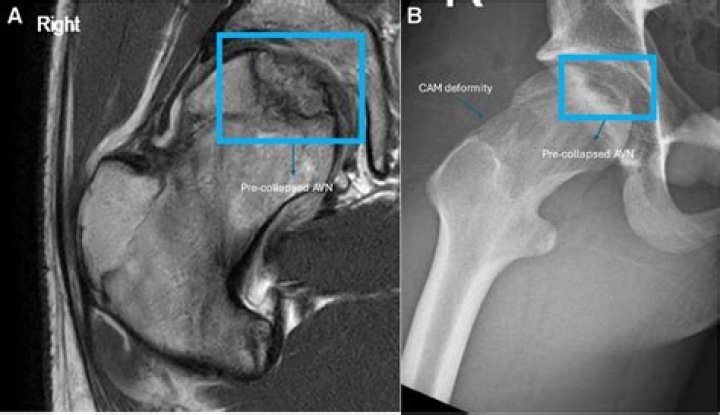

X-rays use electromagnetic waves to create pictures of bones inside the body. A doctor can confirm the presence of osteonecrosis lesions on an X-ray if th...